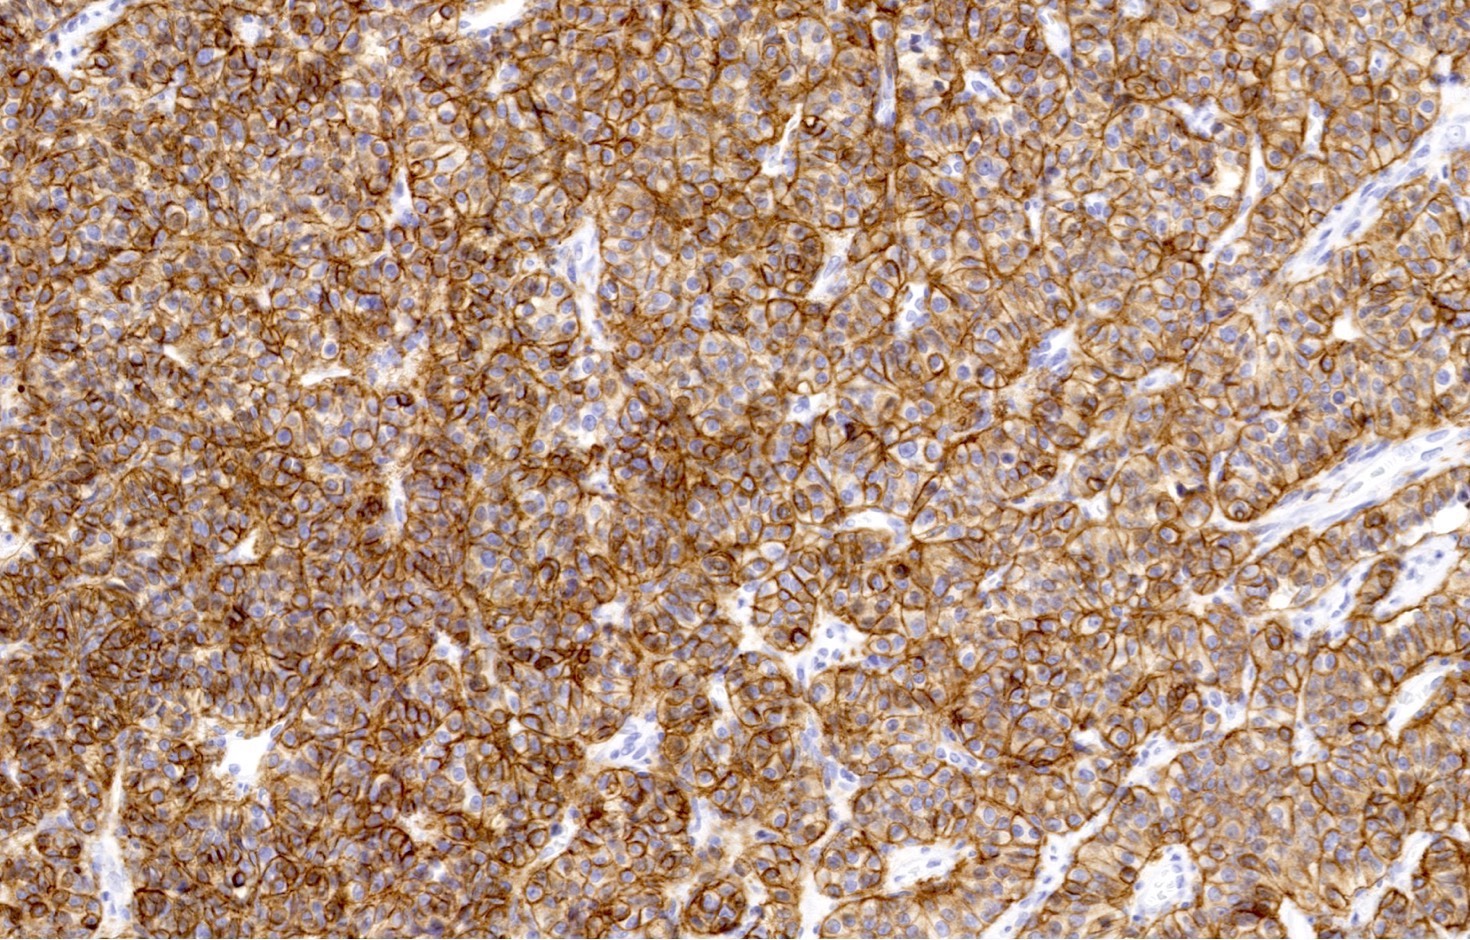

Contributed by Philippe Joubert, M.D., Ph.D., Jijgee Munkhdelger, M.D., Ph.D. and Andrey Bychkov, M.D., Ph.D.

- Chromogranin, synaptophysin, CD56 and INSM1: diffusely and strongly positive (Mod Pathol 2019;32:100)

- Pancytokeratins: positive, useful to distinguish from paraganglioma (Arch Pathol Lab Med 2010;134:1628)

- Ki67 (expected < 20%)

- Ki67 proliferative index does not have an impact on tumor classification; WHO classification states that is desirable to routinely report its value

- Mostly useful to discriminate between high grade neuroendocrine tumors (small cell carcinoma and large cell neuroendocrine carcinoma), on small or crushed biopsies in particular (Arch Pathol Lab Med 2018;142:947)

- Utility of differentiation between typical and atypical carcinoid is not proven (Virchows Arch 2017;470:153)

- TTF1: useful marker of pulmonary lineage in typical and atypical carcinoids but only positive in < 50% of cases

- TTF1+ carcinoids are more commonly seen in peripheral lesions and staining is commonly focal and weak (Hum Pathol 2004;35:825)

- Rb: preserved in the vast majority of pulmonary carcinoids (Transl Lung Cancer Res 2017;6:513)